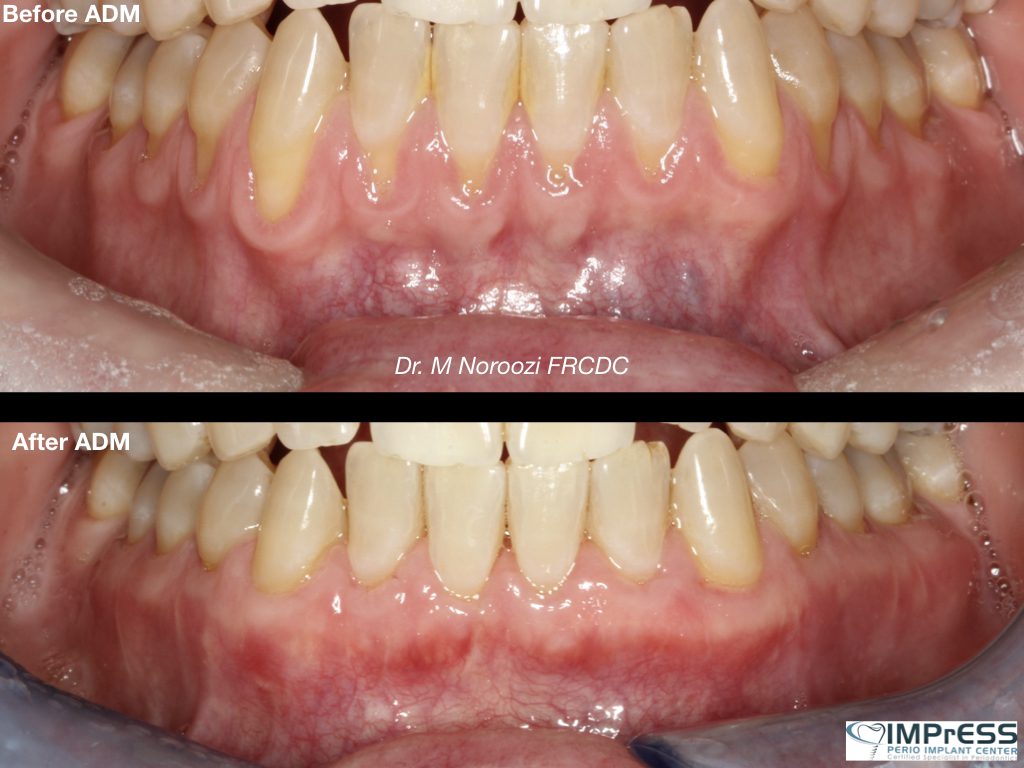

Dr. Mehdi Noroozi, certified Pinhole clinician, performs revolutionary Pinhole® Surgical Technique with application of allograft dermal matrix as an alternative to traditional gum grafting at IMPrESS Perio Implant Center located in Burnaby BC for treatment of gum recessions predictably, safely and minimally invasive. Learn more about our specialist here.

During the Chao Pinhole® Surgical Technique, a needle is used to make a small hole in the patient’s existing gum tissue. Through this pinhole, special instruments are used to gently loosen the gum tissue. These tools help expand and slide the gumline to cover the exposed root structure. There are no grafts, no or minimal sutures, and no incisions needed with the Chao Pinhole® Surgical Technique. It simply involves the adjustment of the existing tissue and thickening of the gingival biotype (Gum) through the placement of collagen or acellular dermal matrix (alloderm).

General Disclaimer: The results in the photographs are examples only and do not imply any certainty of the result of a procedure, and all outcomes are subject to the circumstances of the individual patient.